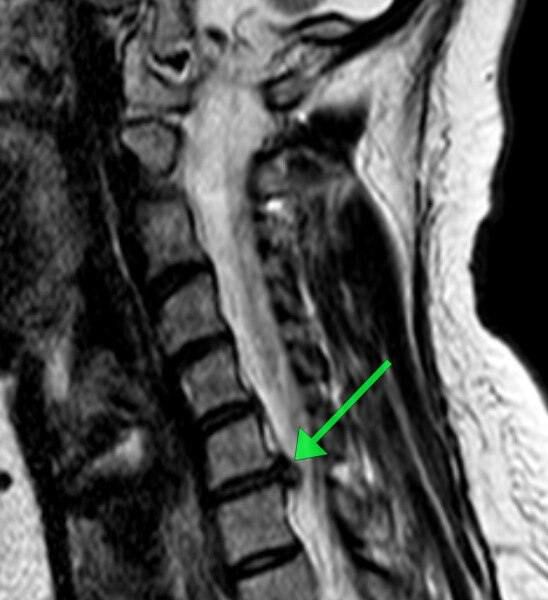

Пациентка обратилась с жлобами на изматывающую боль в руке. Ей провели МРТ, которое показало, что в шейном отделе сформировалась грыжа размером 8 мм. По словам медиков, образование сдавливало спинномозговой канал и корешковое отверстие, угрожая двигательной функции.

«Мы провели сложнейшее микрохирургическое вмешательство, в ходе которого удалили грыжу и стабилизировали позвоночник с помощью современного импланта», — рассказал нейрохирург Николай Карпов, отметив, что операция длилась два часа 20 минут.